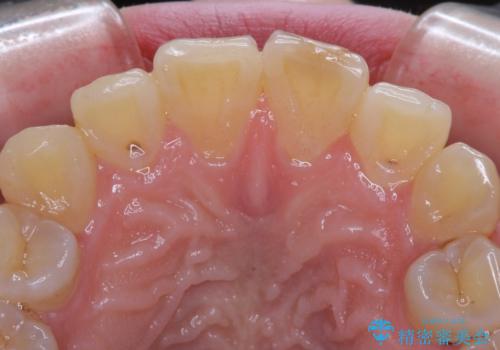

- ぶつけて欠けてしまった前歯を樹脂でつめていたものの、すり減りや変色が顕著とのことで来院された患者様です。

詰め物の詰め直しとオールセラミッククラウンの双方をご提案し、患者様ご希望によりオールセラミッククラウンにて補綴治療を行うこととしました。

歯列全体に表面の着色があったため、クリーニングとホワイトニングを事前に行い、ホワイトニング後1ヶ月ほどおいて、色の落ち着いたところで色合わせを行いました。